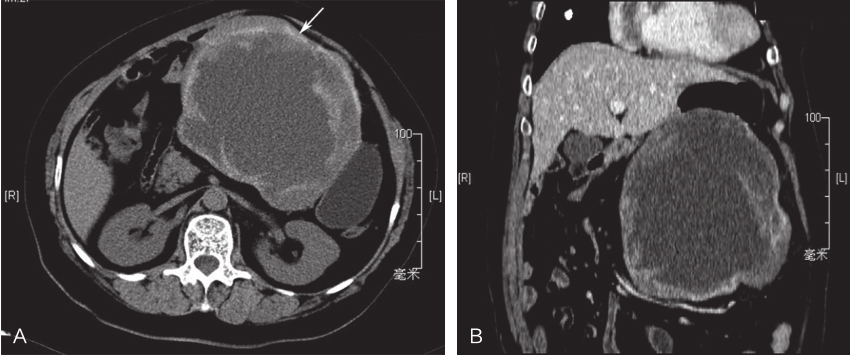

腹盆腔增强CT:肝胃之间巨大囊实性肿块影,形态不规则,边缘可见钙化,内见斑片状较高密度影,大小约13.7cm×15.2cm,增强后强化不明显,与胃小弯侧部分胃壁分界欠清,胃受压移位明显,肝脏表面光滑,各叶比例均匀,肝实质密度未见异常,动态增强后未见异常强化灶,肝内血管分布均匀,走向自然,未见狭窄或充盈缺损;脾脏未见肿大,密度均匀;胆囊壁光滑,未见局限性增厚,胆管未见扩张;胰腺及双侧肾脏无殊;后腹膜未见肿大淋巴结;腹腔内无积液(图1)。

图1腹盆腔CT示肝胃间巨大囊实性肿块

A.水平位;B.冠状位